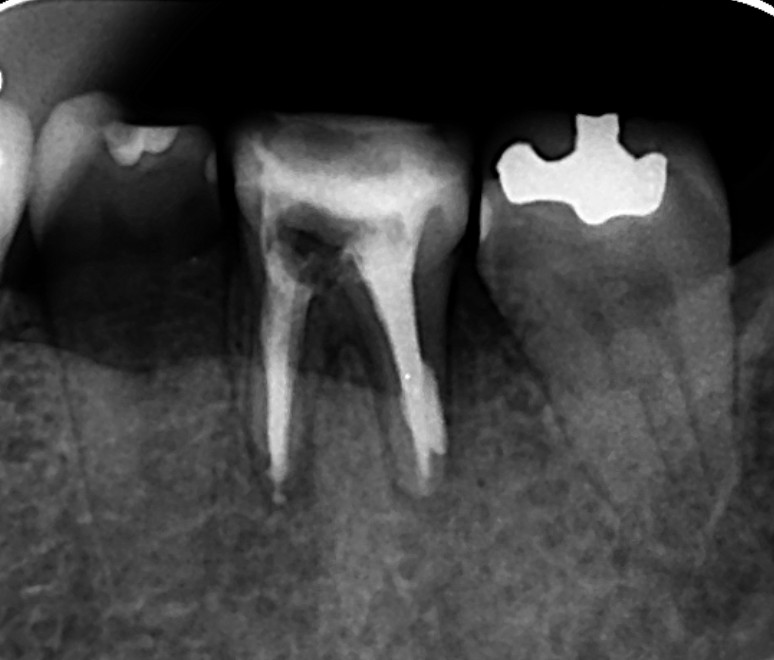

再手術ではなく、精密再根管治療をまず行うことにしました。再根管治療で治せる確率は0ではないと判断しました。画像は、根管充填時のレントゲン写真です。